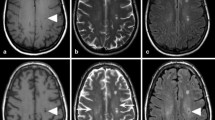

Short Repetition Time (TR) and short Time to Echo (TE) generate T1WI. Fluid appears dark and fat appears bright on T1WI (Fig. 9.2a). T1WI best depict the normal anatomy of brain parenchyma. Grey matter appears intermediate in signal intensity, while white matter appears hyperintense as compared to grey matter. Gadolinium decreases T1 of the tissues and appear bright on T1WI. So, post-contrast images can be used for depiction of vascular changes. In various pathologies such as tumours and inflammation, breakdown of blood–brain barrier can lead to leakage of contrast into the brain parenchyma causing its enhancement and thus localization of pathology on post-contrast T1WI.

Long TR and long TE generate T2WI. Fluid appears bright and fat appears dark on T2WI. Grey matter appears intermediate signal intensity, while white matter appears hypointense as compared to grey matter (Fig. 9.2). As most pathologies are associated with cerebral oedema, i.e. increased signal on T2WI, they are more easily picked up on T2WI.

FLAIR is a special inversion recovery sequence which supresses the cerebrospinal fluid (CSF) (Fig. 9.2). So, it enables us to detect cerebral oedema without glaring high signal from CSF particularly in periventricular regions and in periphery near sulcal spaces. FLAIR sequence is very useful in evaluating various diseases of central nervous system such as infarction, demyelination and subarachnoid haemorrhage in trauma patients [1,2,3]. Post-contrast FLAIR images have been used for evaluating leptomeningeal diseases as early meningitis as it enables us to detect which even subtle meningeal enhancement [4].